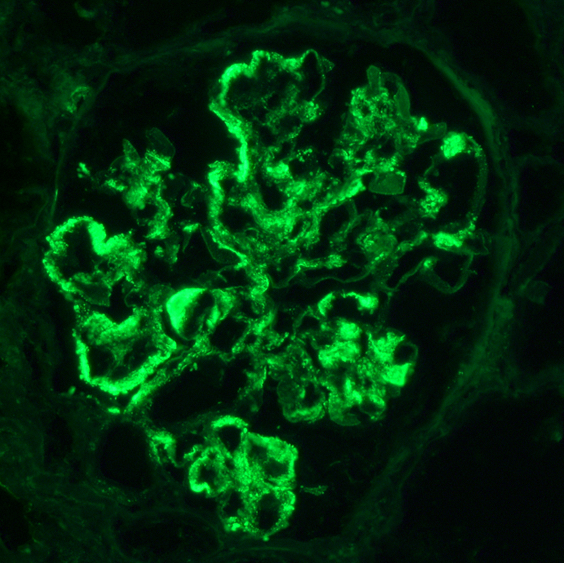

Immunofluorescence description

- Diagnostic criteria: IgG dominant full house immunofluorescence (positive IgG, IgA, IgM, C3, C1q, kappa and lambda light chains)

- Especially important are C1q positivity and extraglomerular immunostaining on the Bowman capsules, arteries, tubular basement membranes and in the interstitium

- Immunofluorescence staining is granular and may be subepithelial, intramembranous, subendothelial or mesangial

- In some cases, antinuclear antibody (ANA) test is seen with antibodies to IgG and the light chains

- Reference: Clin J Am Soc Nephrol 2019;14:1605

Immunofluorescence images

- Immunofluorescence microscopy: Up to 5 nonsclerosed glomeruli are available for evaluation. Mild to high intensity granular immunofluorescence staining was detected in the mesangial areas and less in the capillary walls with antibodies to IgG (4+), IgA (3+), IgM (2+), C3 (4+), C1q (3+), kappa light chains (4+) and lambda light chains (4+). Extraglomerular staining is seen on the arterial walls with antibodies to IgG.